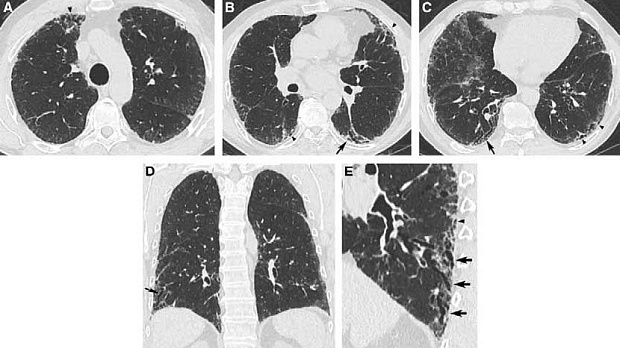

Результаты. Экспертами Рабочей группы обновлены диагностические критерии ИЛФ. Ранее описанные паттерны обычной интерстициальной пневмонии (ОИП) уточнены и обозначены как паттерны ОИП, вероятной ОИП, неопределенный и альтернативный диагнозы. Для больных с впервые выявленным интерстициальным заболеванием легких (ИЗЛ) с паттернами вероятной ОИП, неопределенного или альтернативного диагнозов по данным компьютерной томографии легких высокого разрешения (КТВР) разработана условная рекомендация выполнения бронхоальвеолярного лаважа (БАЛ) и хирургической биопсии легких. Рекомендации «за» или «против» выполнения трансбронхиальной биопсии (ТББЛ) или криобиопсии (КБЛ) легких не разработаны по причине недостаточности доказательств. Напротив, для больных с впервые выявленным ИЗЛ и паттерном ОИП по данным КТВР выработана сильная рекомендация НЕ выполнять хирургическую биопсию, ТББЛ и КБЛ; выработана условная рекомендация против использования БАЛ. Дополнительные рекомендации включают условную рекомендацию по многопрофильному обсуждению и сильную рекомендацию против измерения сывороточных биомаркеров с целью дифференциации ИЛФ от других ИЗЛ.